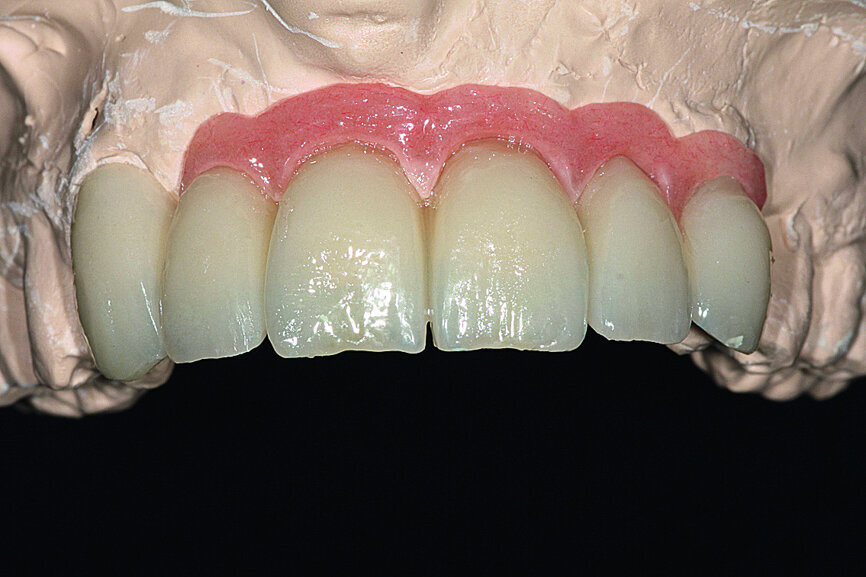

Pre-implant prosthetic study

After four months, according to radiographic examination, the tissue had healed and the bone mass appeared stable (Fig. 10). New impressions were taken to prepare for the next step in treatment: the implant drilling guide. After four months of healing, the increased vestibular bone volume allowed positioning the teeth at the crestal bone and reduction of the false gingiva using additional wax (Fig. 11). A key of the added wax was taken and fabricated in clear casting resin. The implant positions were decided on and finalised by drilling placement holes, determining the exact position of the implants (Fig. 12). The correct positioning of implants in relation to the future prothesis is an important prerequisite for aesthetic and functional success.

This prosthesis serves as a model for the final prosthesis. It is made with easily modifiable material like resin, but with a metal framework to guarantee a certain level of rigidity. In the first step, a model of the framework, which temporarily included the canine to increase stability, was cast in pattern resin (Fig. 21). The model was then scanned (Aadva, GC Tech.Europe; two cameras, 2 MP, precision: 10 μm) before being transferred to a machining centre (GM 1000, GC Tech.Europe; Figs. 22–24). Once back from the machining, the titanium framework was tested on the working model and its stability was verified (Figs. 25 & 26).

The cosmetic material (UNIFAST III resin; surface rendering: OPTIGLAZE color, GC Tech.Europe) was then placed on the framework (Fig. 27). The bone graft permitted a maximum reduction of the vestibular false gingiva.